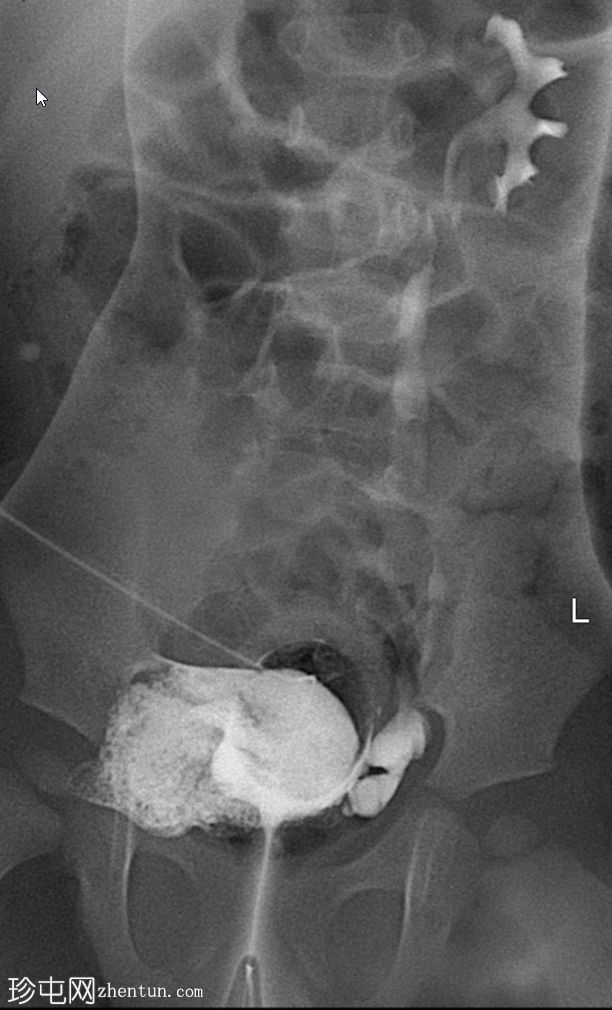

斜位片(纱布阻塞)

可见脐尿管开口通畅;在充盈期,造影剂经脐尿管自由流出,导致膀胱充盈不足。经脐尿管开口置入Foley导尿管并充盈球囊;然而,造影剂持续渗漏,膀胱充盈仍然不足。

使用纱布进行外部压迫成功阻塞了脐尿管开口,膀胱充盈良好。左侧输尿管和肾盂肾盏系统可见膀胱输尿管反流,符合II/III级VUR。输尿管轮廓正常,无憩室,无管壁增厚。尿道显影正常,未见后尿道瓣膜或狭窄。无肾积水。